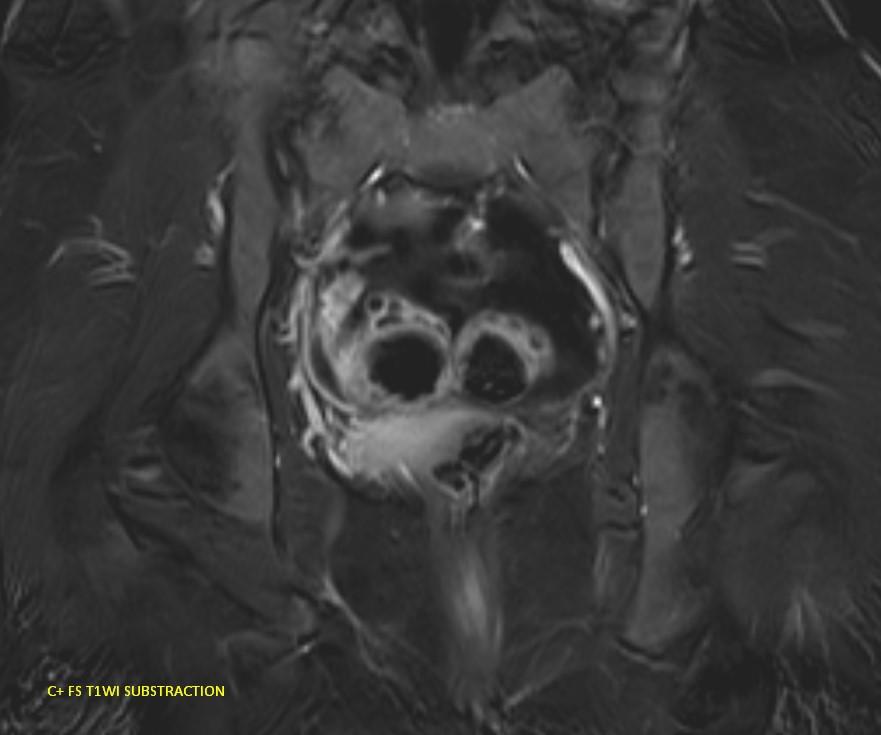

*23-year-old female with primary infertility.

Answer: Kissing Ovary Sign

MR images demonstrating the kissing ovaries, bilateral endometriomas (chocolate cysts), and peritoneal inclusion cyst (peritoneal pseudocyst).

Blood products in ovaries may cause adhesions to pull the ovaries toward the midline. This is considered a sign of pelvic endometriosis (1).